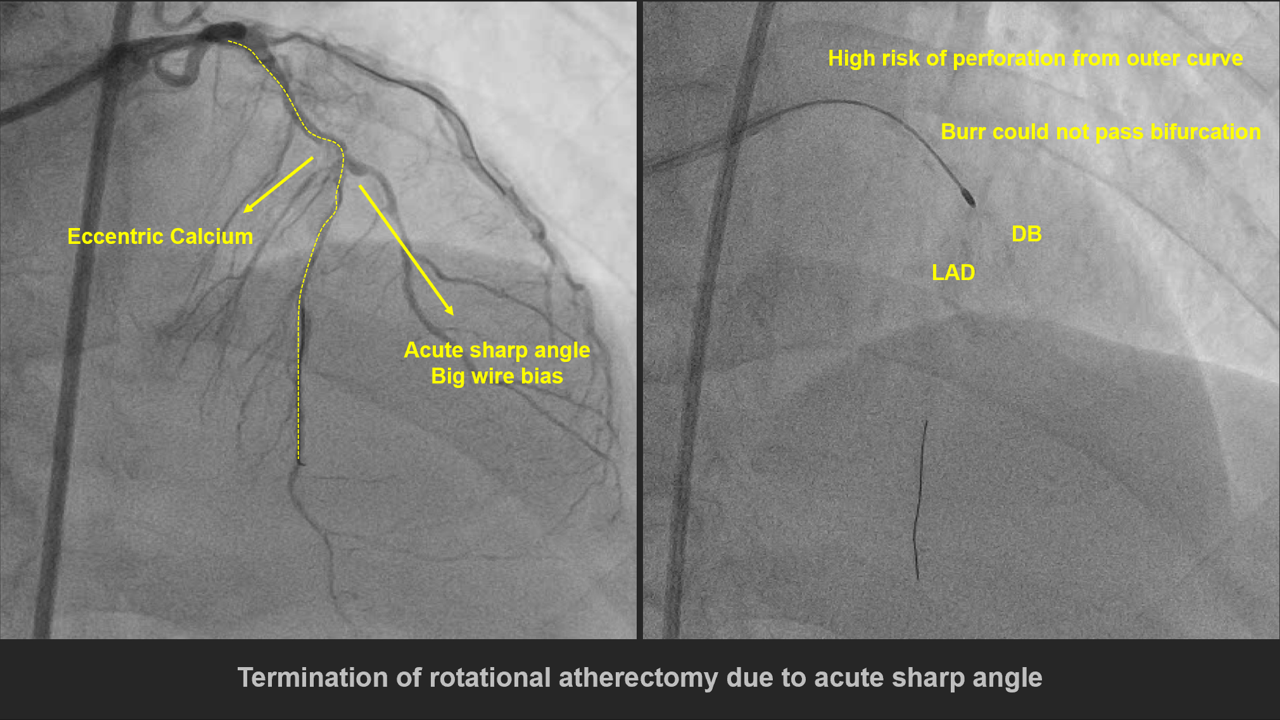

1. V-A mode ECMO was used for CHIP PCI 2. 1.5mm balloon was advanced to m-LAD 3. 2.0mm balloon failed to cross the heavycalcified lesion at m-LAD 4. By Extra support rota wire, 1.25mm Burradvanced to the lesion in a slow and steady manner (163300-182000 rpm). p-LADlesion was polished, however, Burr could not pass through m-LAD tortuous andheavy calcified bifurcation lesion. To avoid high risk of perforation, weterminated the Rotational Atherectomy 5. 1.5mm balloon was advanced to m-LADlesion 6. 2.0 balloon failed to deliver to the M/3LAD tortuous and heavy calcified bifurcation lesion, even under 5.5 FrGuideLiner or Buddy wire technique 7. 2.0mm balloon was advanced to m-LAD throughDB wire, inflated at pressure 22-24 atm 8. 2.0mm Cutting balloon was advanced tothe lesion through DB wire, inflated at pressure 6-18 atm 9. 2.0mm balloon was advanced to the lesionthrough DB wire 10. A 2.0 balloon successfully advanced to mto d-LAD 11. 2.0mm Cutting balloon was advanced tothe lesion through LAD wire, inflated at pressure 8-18 atm 12. 2.5mm balloon was advanced to m-LADlesion 13. 2.0x30mm Onyx stent failed to adavnceto the lesion, even under GuideLiner 6Fr 14. Finally 2.0x30mm Onyx stentsuccessfully advanced to the proper segment at m-LAD under Wiggle wire support 15. 2.5x28mm Xience Sierra stent wasdeployed at p-Ramus 16. 2.75x30mm Onyx stent was deployed at LMto m-LAD 17. Final angiography showed TIMI 3 distalflow & No extravasation

Case Summary